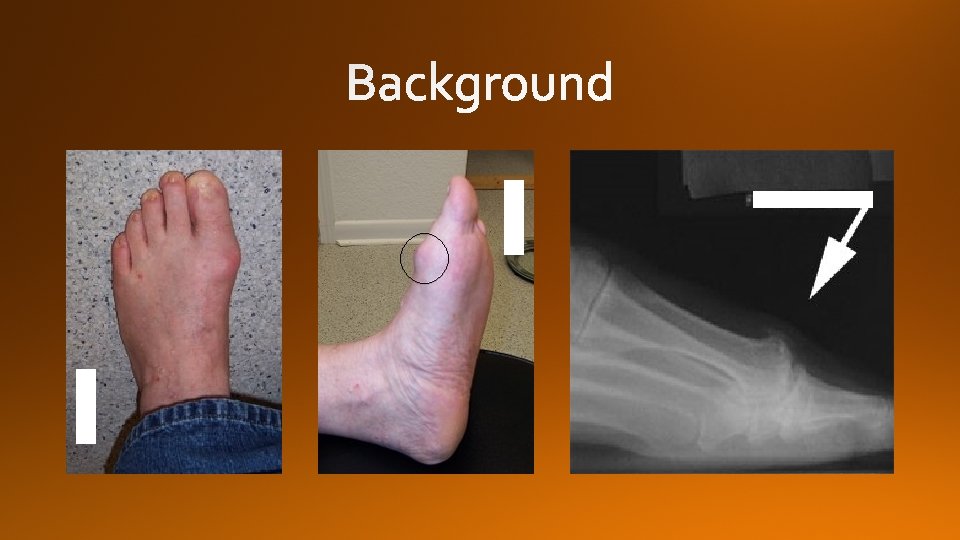

Hallux Rigidus

Grade Examination findings Xray findings 0 Stiffness normal 1 Mild pain at extremes of motion mild dorsal osteophyte, normal joint space 2 Moderate pain with range of motion increasingly more constant moderate dorsal osteophyte, <50% joint space narrowing 3 Significant stiffness, pain at extreme ROM, no pain at mid-range severe dorsal osteophyte, >50% joint space narrowing 4 Significant stiffness, pain at extreme ROM, pain at mid-range of motion severe dorsal osteophyte, >50% joint space narrowing